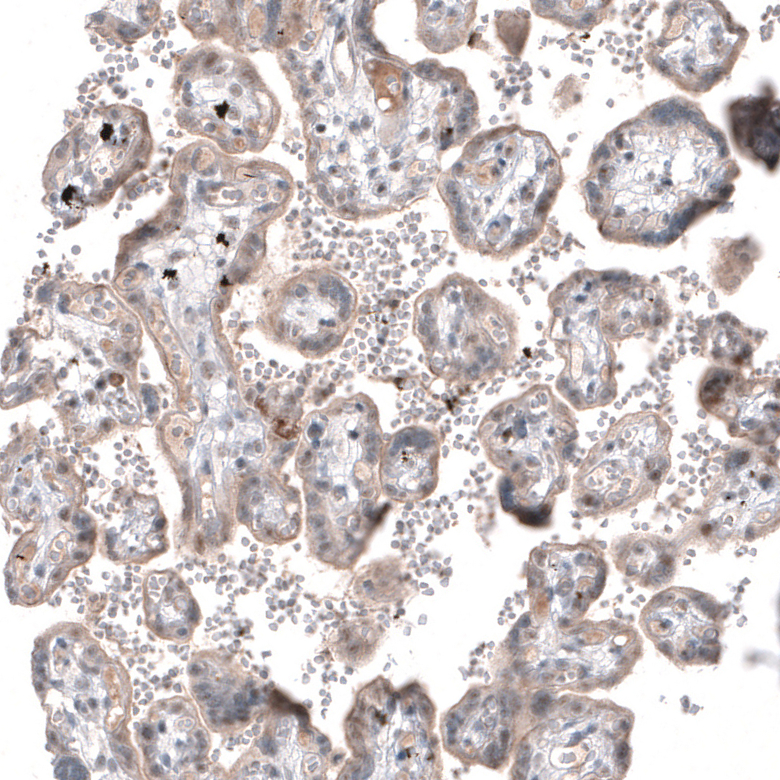

Immunohistochemical staining of human testis shows moderate membranous positivity in cells in seminiferous ducts.